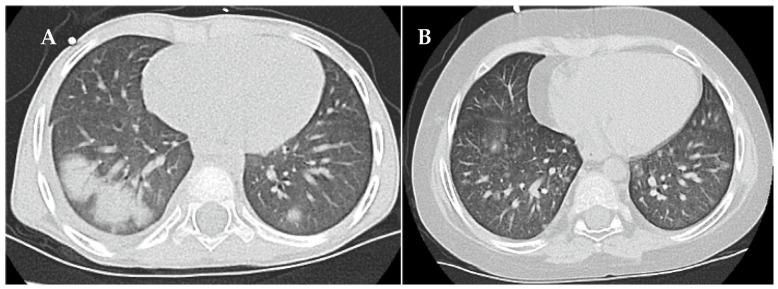

在高危神经母细胞瘤患者进行自体造血干细胞救援之前,将细胞毒性药物白消安纳入大剂量化疗方案可提高与这种致命疾病作斗争的儿童的生存率。然而,白消安引起的毒性可能很严重。在此,我们描述了两名高危神经母细胞瘤儿童因按总体重调整白消安治疗而导致的急性肺损伤的诊断和成功治疗。患者1在白消安治疗后第60天和第100天出现危及生命的双相性急性呼吸衰竭,需要插管和有创机械通气。尽管进行了强化抗炎和免疫调节治疗,包括全身用皮质类固醇、局部吸入方案、阿奇霉素、尼达尼布和体外光化学疗法,患者1仍需要延长的重症监护措施和无创呼吸支持,总共持续了20个月。高分辨率计算机断层扫描显示弥漫性肺泡和间质模式。患者2在白消安治疗后第52天出现部分呼吸衰竭,血氧饱和度不足和呼吸困难。经过6个月的全身用皮质类固醇、局部吸入方案和阿奇霉素治疗后症状得到缓解。高分辨率计算机断层扫描显示非典型肺炎改变伴磨玻璃影。虽然两名患者均完全康复且无肺纤维化迹象,但癌症治疗不得不暂停,然后进行调整,直到从白消安引起的肺损伤中完全康复。白消安引起的肺损伤需要及时诊断和干预。症状和体征是非特异性的,难以与其他原因区分开来。治疗性白消安药物水平监测以及通过编码白消安代谢主要酶的谷胱甘肽S-转移酶α1基因中的启动子多态性来识别药物过量风险患者,有望降低白消安引起的毒性风险。